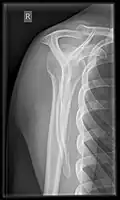

Fracture

Fractures of shoulder bones can include clavicular fractures, scapular fractures, and fractures of the upper humerus.

Conventional x-rays and ultrasonography are the primary tools used to confirm a diagnosis of injuries sustained to the rotator cuff. For extended clinical questions, imaging through Magnetic Resonance with or without intraarticular contrast agent is indicated.

Hodler et al. recommend starting scanning with conventional x-rays taken from at least two planes, since this method gives a wide first impression and even has the chance of exposing any frequent shoulder pathologies, i.e., decompensated rotator cuff tears, tendinitis calcarea, dislocations, fractures, usures, and/or osteophytes. Furthermore, x-rays are required for the planning of an optimal CT or MR image.[25]

X-ray

Projectional radiography views of the shoulder include: